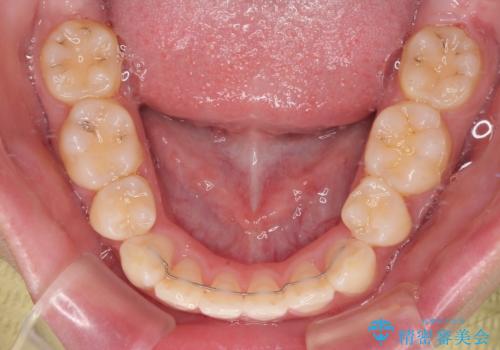

- 前歯部のデコボコと口元が出ているのが気になるとのことで来院された患者様です。

口元の突出感の解消と、このままデコボコを解消するとさらに出っ歯傾向になってしまうことを考慮し、上下左右の小臼歯を抜歯しクリアブラケットにて矯正していくこととしました。

舌突出癖を改善するトレーニングを一生懸命やっていただいたおかげで2年以内に治療を終えることができました。